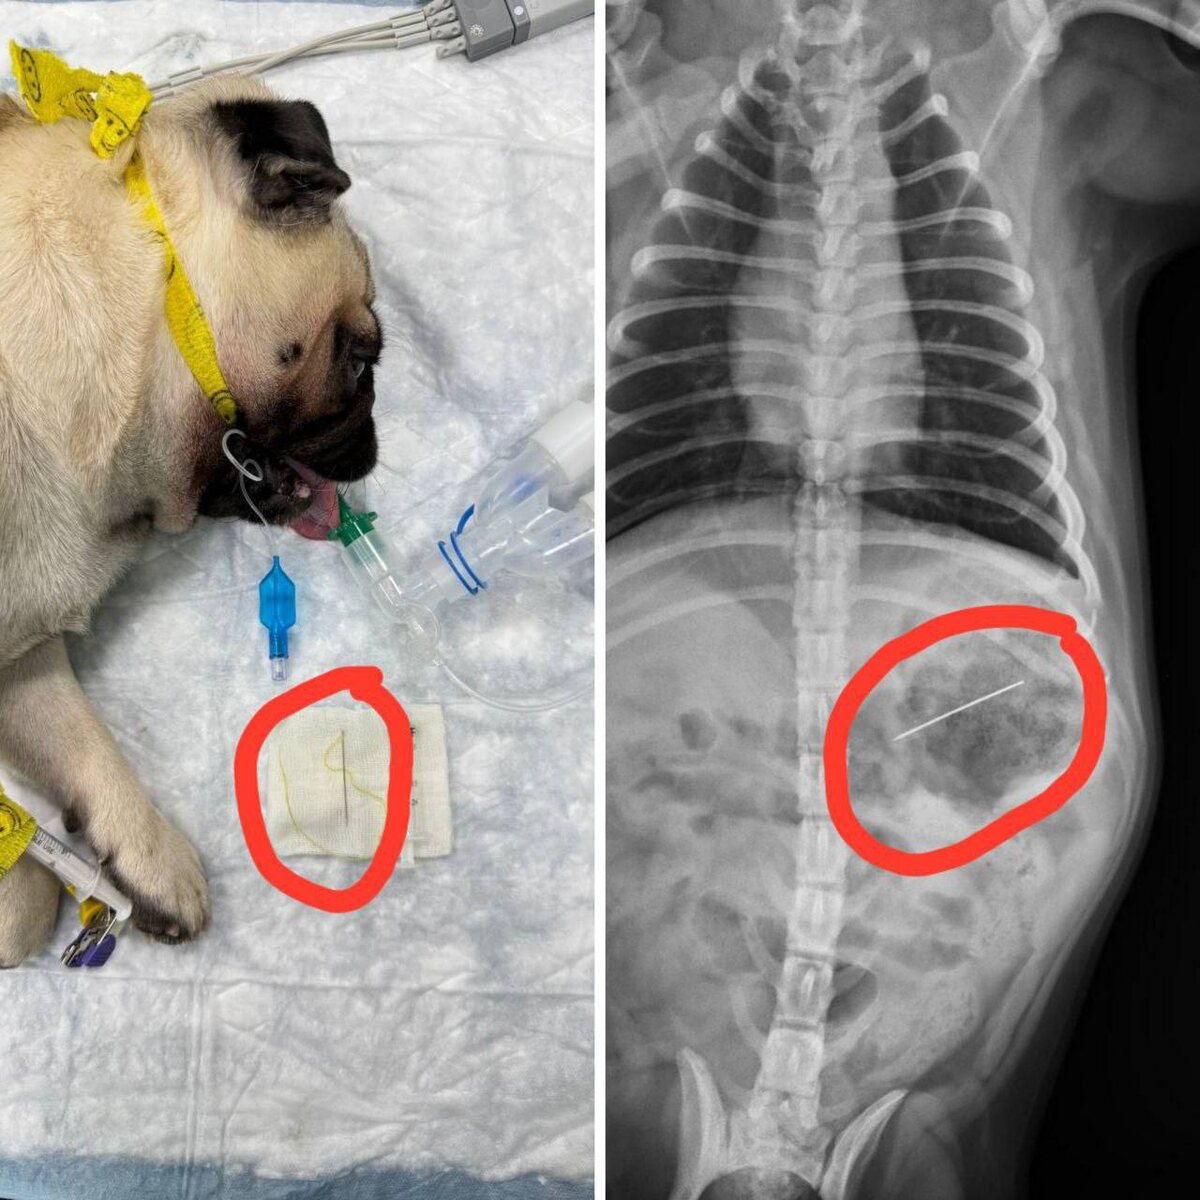

В Липецке мопс умудрился проглотить иголку с ниткой. Хозяева сразу обратились к ветеринарам. К счастью, врачи успели вовремя: они обнаружили опасный предмет в желудке и извлекли его при помощи эндоскопа, избежав сложной операции. Сейчас питомец чувствует себя хорошо, а специалисты напоминают — держите иголки, нитки и мелкие предметы подальше от домашних животных.

К счастью, врачи успели вовремя: они обнаружили опасный предмет в желудке и извлекли его при помощи эндоскопа, избежав сложной операции.

Сейчас питомец чувствует себя хорошо, а специалисты напоминают — держите иголки, нитки и мелкие предметы подальше от домашних животных.